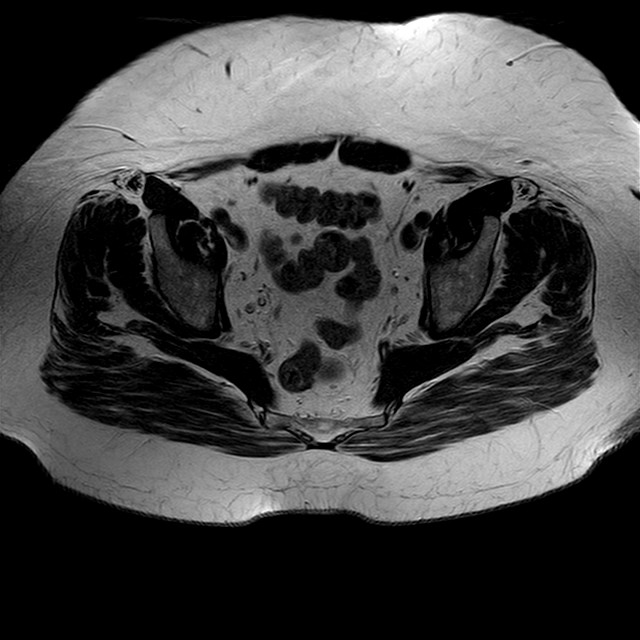

Esami: RMN BACINO

eT2w TSE

Evidenti e simmetriche alterazioni osteofitosiche in regione coxo femorale con riduzione delle rime articolari. Degenerazione completa del cercine glenoideo. Non attuali segni di versamento articolare. Non segni di edema osseo che escludono attuale algodistrofia od osteonecrosi. Lieve e simmetrica riduzione del trofismo della muscolatura glutea.